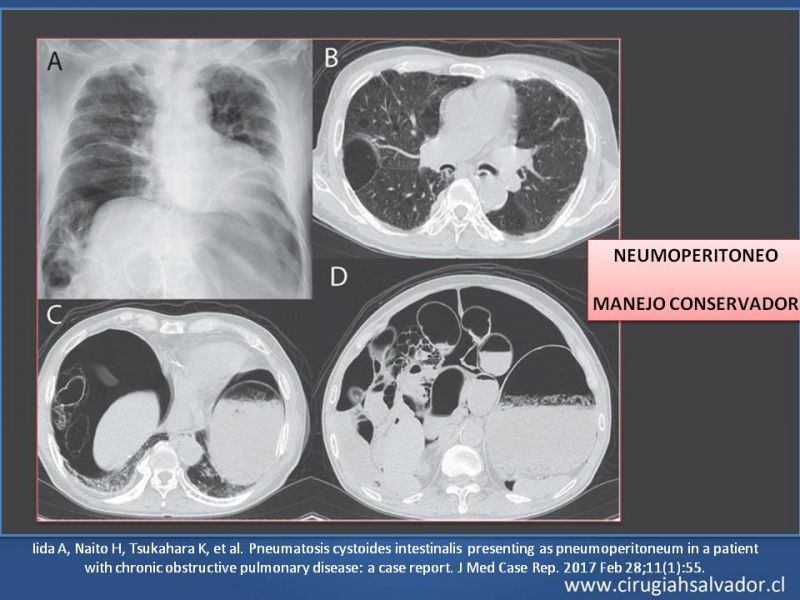

Neumatosis Intestinal